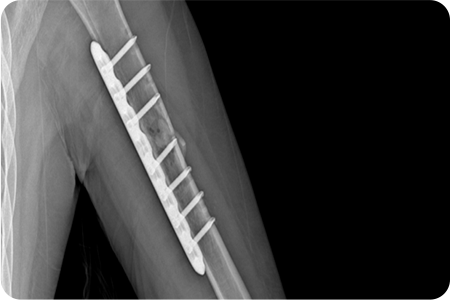

상완골 골절 수술

X-ray 및 CT를 통해 골절 형태와 전위 정도를 확인합니다.

골절된 뼈를 원래 위치로 맞추는 정복 작업을 진행합니다.

금속판, 나사, 고정막을 이용해 뼈를 고정합니다.